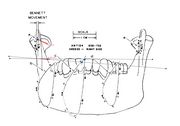

| 15:43, 13 October 2024 | FIGURE 3 (ACCORNERO).jpg (file) |  |

750 KB | Gianni | 1 | |